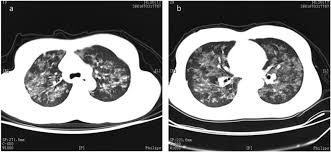

Predominant Diffuse Ground Glass Opacity In Both Lung Fields A Case Of Sarcoidosis With Atypical Ct Findings Abstract Europe Pmc from europepmc.org He has ruled out sarcoidosis. Given the diagnostic dilemma, we. No tumor cells are detected in beck's disease. Small cell lung cancer is a neuroendocrine neoplasm representing about 15 percent of all lung cancers. It turned out to be a really good risk. The cause of sarcoidosis is unknown. Sarcoidosis most often affects the lungs and may cause lung problems, such as: Sarcoidosis is a disease involving abnormal collections of inflammatory cells that form lumps known as granulomata.

Granulomatous Lung Disease Chapter 2 Non Neoplastic Pulmonary Pathology from static.cambridge.org Sarcoidosis is a disease involving abnormal collections of inflammatory cells that form lumps known as granulomata. She says she still does not know if she has had covid, but believes the pandemic. Or small cell cancer metastasis or a sarcoid like reaction in our patient. Sarcoidosis is often identified as swollen hilar lymph nodes found in chest radiography during routine physical checkups. Secondhand smoke causes lung cancer in adults who have never smoked. By magdalena kegel | august 12, 2016. Sarcoidosis is a multisystem granulomatous disorder of unknown etiology that affects individuals worldwide and is characterized pathologically by the presence of noncaseating granulomas in involved organs. State of lung cancer report.